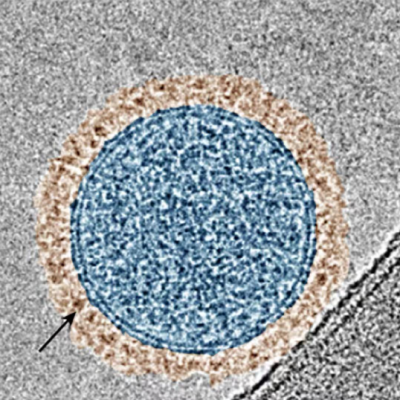

West and colleagues in Duke’s Nicholas School of the Environment and the Department of Chemistry at Trinity College of Arts and Sciences found that nanoparticles of the plastic polystyrene -- typically found in single use items such as disposable drinking cups and cutlery -- attract the accumulation of the protein known as alpha-synuclein. West said the study’s most surprising findings are the tight bonds formed between the plastic and the protein within the area of the neuron where these accumulations are congregating, the lysosome.

Researchers said the plastic-protein accumulations happened across three different models performed in the study - in test tubes, cultured neurons, and mouse models of Parkinson’s disease. West said questions remain about how such interactions might be happening within humans and whether the type of plastic might play a role.